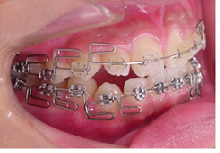

この過程で歯並びが整いMEAW(マルチループ)を装着しやすくなります。

MEAW(マルチループ)を使用する事で、上顎前突(出っ歯)や咬合高径(咬み合わせの高さ)の改善をしています。

☆治療途中

MEAW(マルチループ)を使用する事で、上顎前突(出っ歯)や咬合高径(咬み合わせの高さ)を改善して2年6ヶ月で非抜歯での治療で綺麗な歯並びになりました。

☆終了時